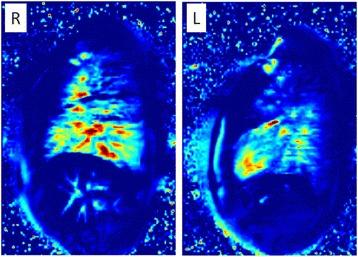

Bronchiectasis is a common feature of severe inherited and acquired pulmonary disease conditions. Among inherited diseases, cystic fibrosis (CF) is the major disorder associated with bronchiectasis, while acquired conditions frequently featuring bronchiectasis include post-infective bronchiectasis and chronic obstructive pulmonary disease (COPD). Mechanistically, bronchiectasis is driven by a complex interplay of inflammation and infection with neutrophilic inflammation playing a predominant role. The clinical characterization and management of bronchiectasis should involve a precise diagnostic workup, tailored therapeutic strategies and pulmonary imaging that has become an essential tool for the diagnosis and follow-up of bronchiectasis. Prospective future studies are required to optimize the diagnostic and therapeutic management of bronchiectasis, particularly in heterogeneous non-CF bronchiectasis populations.

支气管扩张症是严重遗传性和获得性肺部疾病的常见特征。在遗传性疾病中,囊性纤维化(CF)是与支气管扩张症相关的主要疾病,而获得性疾病常伴有支气管扩张症,包括感染后支气管扩张症和慢性阻塞性肺疾病(COPD)。从机制上讲,支气管扩张症是由炎症和感染的复杂相互作用驱动的,中性粒细胞炎症起着主要作用。支气管扩张症的临床特征和管理应包括精确的诊断性检查、量身定制的治疗策略和肺部成像,这已成为支气管扩张症诊断和随访的重要工具。需要前瞻性的未来研究来优化支气管扩张症的诊断和治疗管理,特别是在异质性非 CF 支气管扩张症人群中。